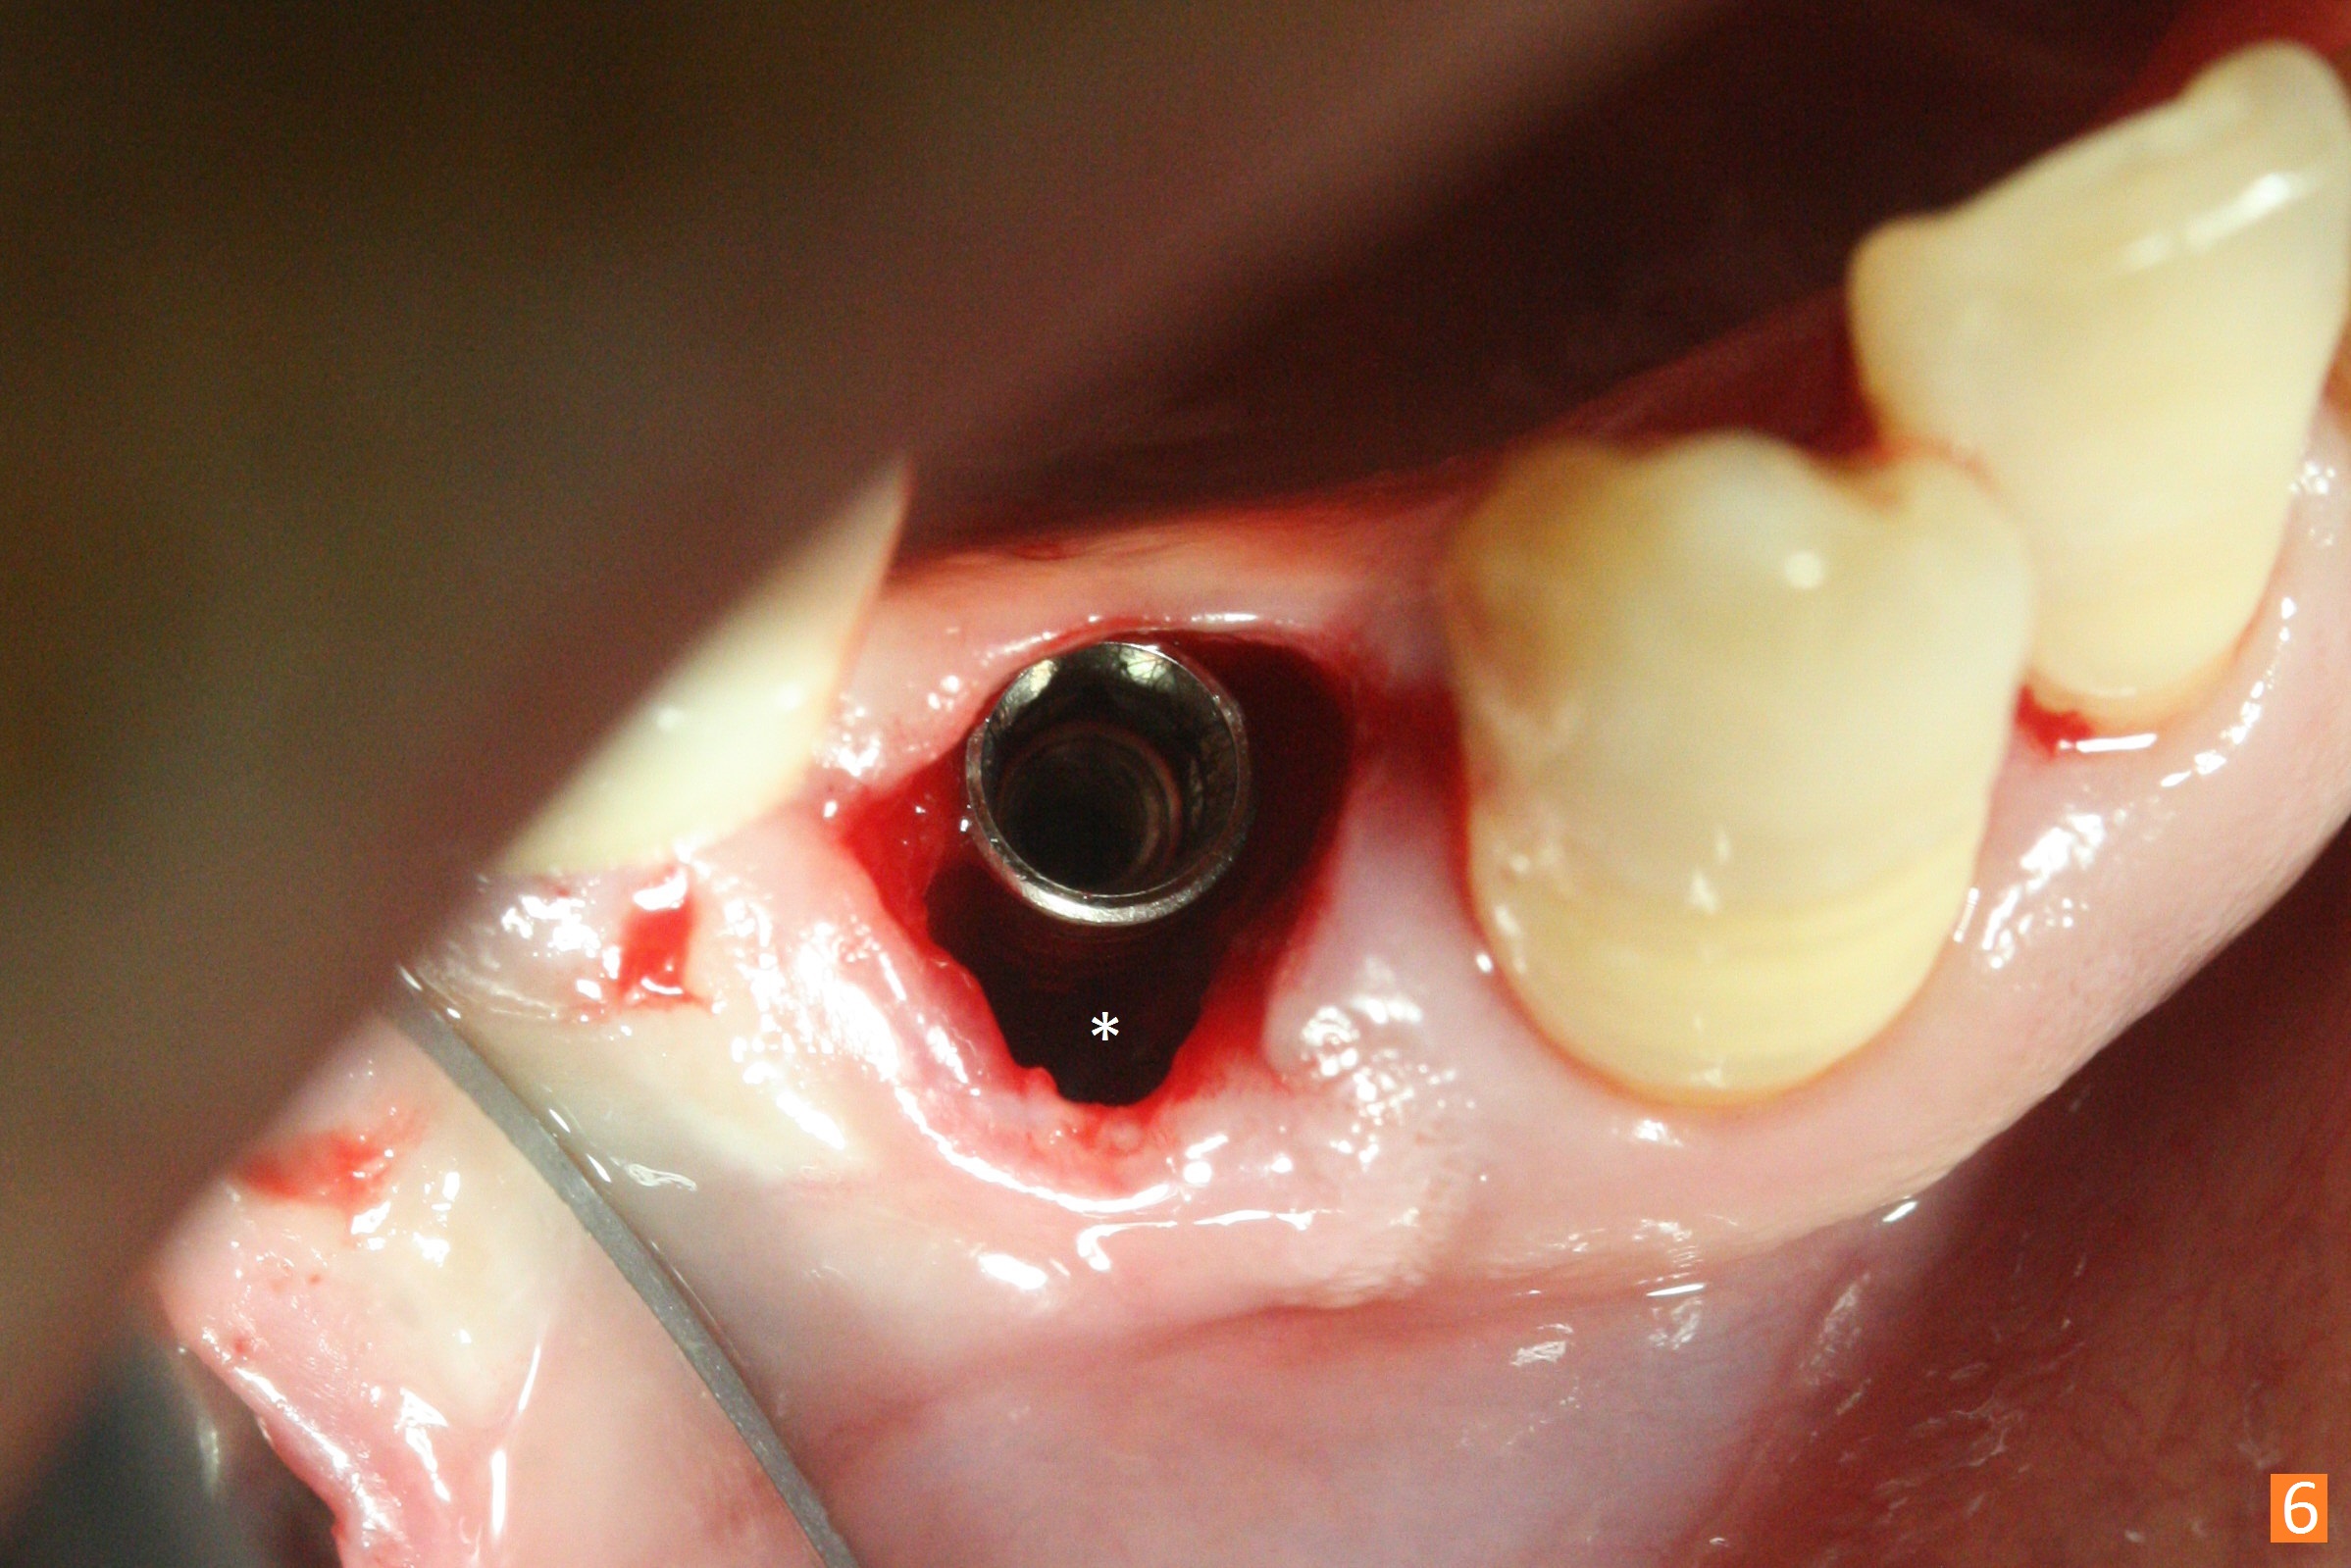

The affected tooth (#28) has buccal gingival recession (Fig.1). As expected, the buccal plate is found low after extraction. Osteotomy is established in the lingual slope of the socket with 1.5 mm drill for 13 mm (Fig.2,3). Following use of Magic Drill 3.3 mm for 13 mm, a 4x11 mm dummy implant is incompletely seated (Fig.4); it is also close to the Mental Loop (Fig.4 red line). After use of Final Drill, a 4x9 mm IBS implant is placed 4 mm and 2 mm subgingival buccal and lingual, respectively (Fig.5) with a large buccal gap (Fig.6 (40 Ncm)). After placement of allograft in the peri-implant space (Fig.7 *), a 4.5x5.7(4) mm abutment is placed (A). A piece of gauze is placed in the remaining buccal space prior to provisional fabrication (Fig.8 *). The space occupied by the gauze is later filled with collagen plug before provisional seating. The gingiva is healthy around the provisional 12 days postop (Fig.9). To reduce buccal gingival recession, the buccal margin of the provisional is shortened 4.5 months postop (Fig.10 arrow). PA taken 5.5 months postop is shown with the implant at 31. The lingual gingiva is erythematous, edematous, and recessive with +BOP and deep pockets 14 months postop (Fig.11). It appears that the small and short implant is not favorable for healing. The infected implant is removed with the missing buccal plate; bone graft is placed 15 months postop (7 months post cementation, Fig.12,13).